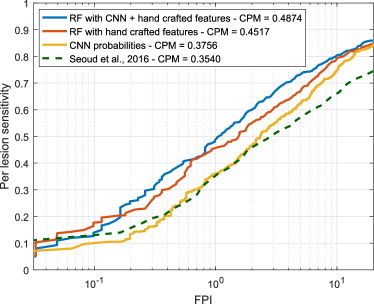

Free-response ROC (FROC) curves were used to evaluate the performance of our red lesion detection method on a per lesion basis. These plots, which are extensively used in the literature to estimate the overall performance on this task, represent the per lesion sensitivity against the average number of false positive detections per image (FPI) obtained on the data set for different thresholds applied to the candidate probabilities. Thus, FROC curves provide a graphical representation of how the model is able to deal with the detection of true lesions in all the images of the data set. We also computed the Competition Metric (CPM) as proposed in the Retinopathy Online Challenge (Niemeijer et al., 2010), which is the average per lesion sensitivity at the reference FPI values . The protocol used by Seoud et al. (2016) was followed when evaluating in DIARETDB1, as indicated in Section 3.1.

Experiment 1 evaluates the model ability to deal with both MAs and HEs simultaneously at multiple scales, following the same protocol as Seoud et al. (2016) (Figure 7). Results obtained by Seoud et al. (2016) were provided by the authors and obtained using the same training and test configuration, and are included for comparison purposes. Hypothesis tests show a statistically significant improvement in the per lesion sensitivity values when using the combined approach compared to using each representation separately ( and for the CNN probabilities and the hand crafted features, respectively). Moreover, the hybrid method reported better results compared to Seoud et al. ().

Table 5 summarizes the CPM values obtained for each experiment and each feature combination, and also using each of the two recently published state-of-the-art methods. Per lesion sensitivities at FPI, which is considered a clinically relevant number of false positives (Niemeijer et al., 2010) are also provided.

When analyzing each individual characterization approach, it is possible to see in Experiment 1 that both the RF trained with hand crafted features and the CNN achieved higher per lesion sensitivities than the method by Seoud et al. (2016) ( and , respectively). This is likely due to the fact that our method for extracting candidates differs from the one used by the alternative approach. Moreover, Seoud et al. (2016) eliminate the lesion candidates occurring within an estimated area around the optic disc center, which is determined using an automated approach. As a consequence, if the diameter of the optic disc is accidentally overestimated by such a method, candidates within valid regions will be suppressed and it will not be possible to recover them afterwards during the classification stage. As seen in Figures 14 and 15, our combined approach is able to discriminate the candidates within the optic disc area and the vascular structures. Hence, instead of using a rigid elimination step based on optic disc segmentation, we let the classifier to decide whether a candidate is actually a true positive or a false positive occurring on an anatomical region. This approach increases the maximum achievable per lesion sensitivity on each image, allowing to train our classifier with a larger amount of false positive lesions and to get a higher sensitivity in test time. A similar observation can be made from the results of Experiment 2, in which the hand crafted features and the deep learning based approach reported higher per lesion sensitivities than those reported by Wu et al. (2017). It must be underlined, also, that the Wu et al. (2017) method was trained on the first half of the images with pathologies on e-ophtha and evaluated on the second half, rather than trained on a separate data set and evaluated on the complete set, as in our case. Moreover, it is worth noting that the images of the healthy patients were also included during evaluation to get a more accurate estimation of its actual performance on a real, clinical scenario.